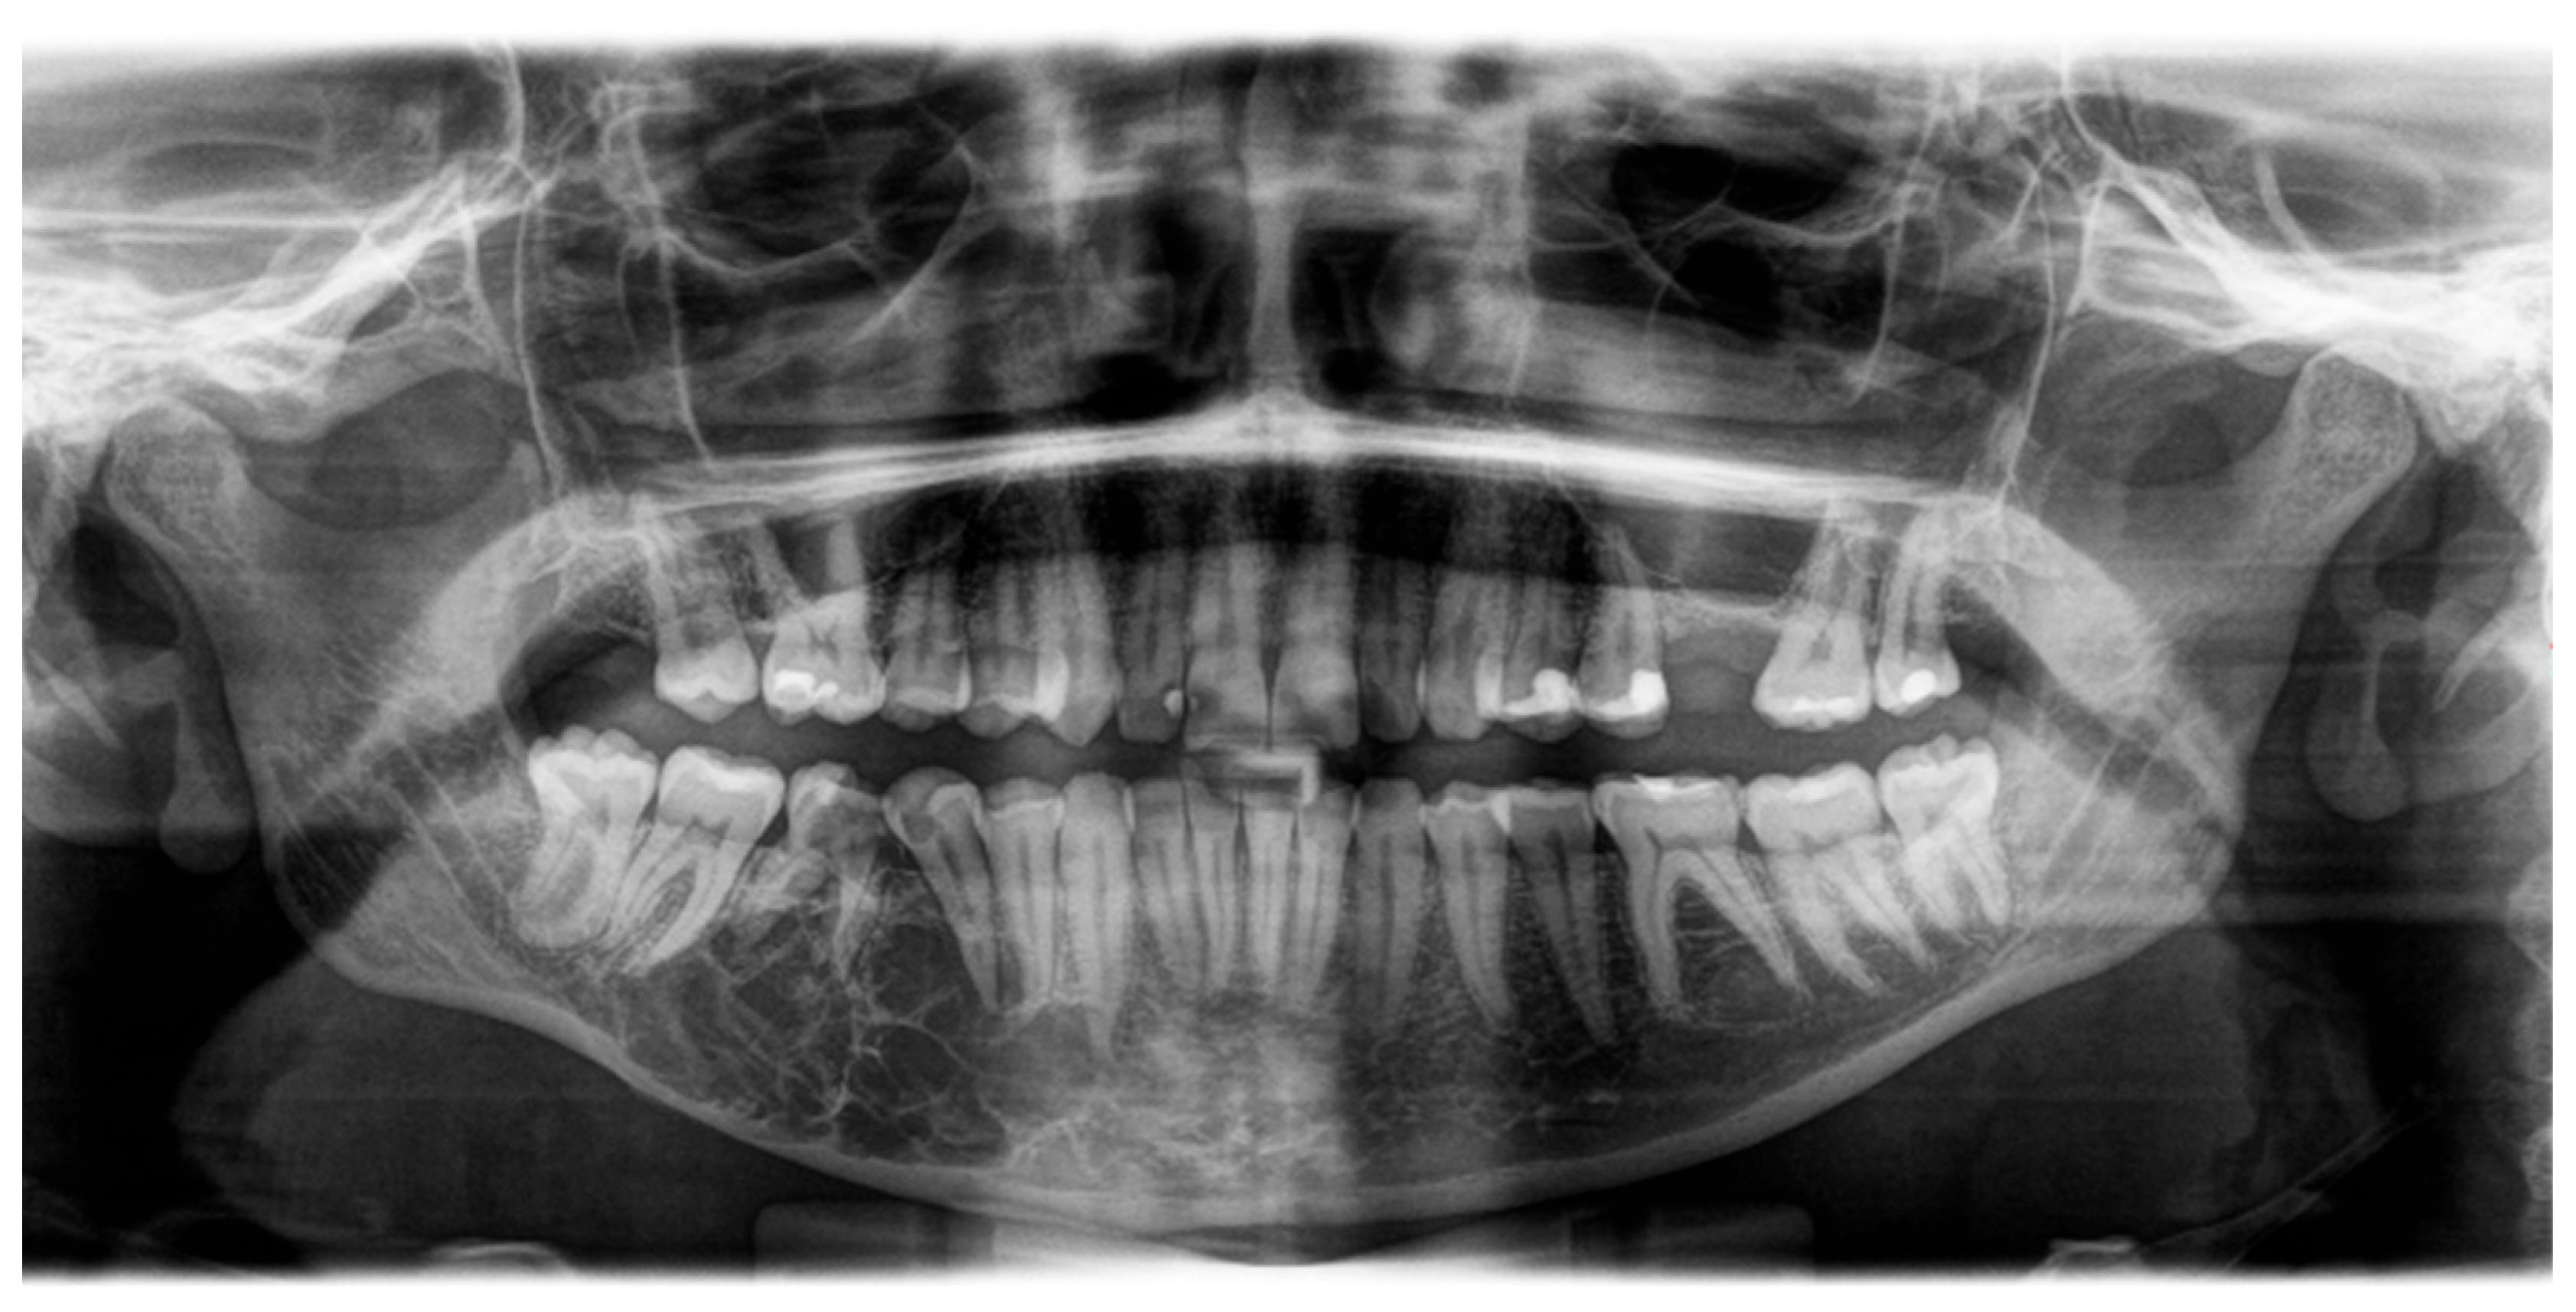

2.1. Examination

| Radiographic | “Soap-bubble”, “ground-glass” or “tennis racquet strings” patterns complicating the diagnosis | [4,12,14] |